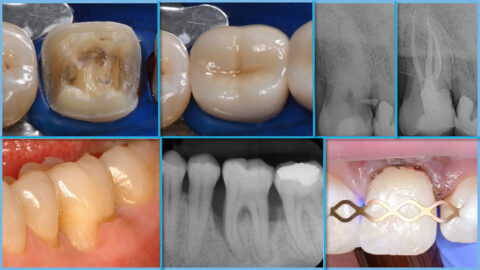

Der Studiengang Zahnerhaltung ist ein berufsbegleitender Weiterbildungsstudiengang mit dem Abschluss Master of Science (M.Sc.). Er bietet eine klinisch orientierte Ausbildung nach den aktuellsten evidenzbasierten Standards und entsprechend der Leitlinien der wissenschaftlichen Fachgesellschaften. Während des Studiums werden die Bereiche der Restaurativen Zahnerhaltung, der Parodontologie, der Endodontologie sowie der Präventiv- und Kinderzahnmedizin in Theorie und Praxis vermittelt. Die Regelstudienzeit beträgt 5 Semester.

Zentraler Bestandteil des Studiengangs ist die Arbeit an und mit Patientenfällen aus der Praxis. Die praktische Tätigkeit setzt jedoch die Einbettung der klinischen Fälle in den aktuellen wissenschaftlichen Kontext voraus, der in den entsprechenden Modulen erarbeitet wird.

Dabei wird in Vorlesungen Wissen vermittelt, das deutlich über die während des Studiums der Zahnmedizin vermittelten Grundlagen hinausreicht. Regelmäßige Fallpräsentationen und -besprechungen schulen den Transfer und ermöglichen den Austausch mit Kolleginnen und Kollegen. Die entsprechenden klinischen Fälle werden entsprechend eines Fallkataloges dokumentiert, als Präsentationen vorgestellt und gemeinsam diskutiert. Trainingskurse mit Demonstrationen und Hands-on-Übungen in Simulationen ergänzen die Lehrformate und ermöglichen die Weiterentwicklung Optimierung klinischer Techniken und Fertigkeiten.

In den ersten vier Semestern werden die Fächer der Zahnerhaltung gelehrt: Restaurative Zahnerhaltung, Parodontologie, Endodontie, Präventive und Kinderzahnmedizin. Im fünften Semester folgt die Masterarbeit. Während des Semesters finden jede Woche Vorlesungen und klinische Fallbesprechungen statt, die im Hybridformat durchgeführt werden. Das Hauptaugenmerk liegt auf der Patientenbehandlung, die in der eigenen Praxis durchgeführt wird. Dabei soll in jedem der vier Fächer ein vorgegebener Behandlungskatalog erfüllt werden. Die Fälle werden nach vorgegebener Form dokumentiert sowie in den Fallbesprechungen durchgenommen und diskutiert. Pro Semester gibt es jeweils freitagnachmittags 2-3 Hands-on Kurse, deren Termine vorab festgelegt werden.